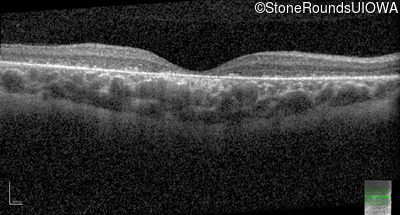

Optical Coherence Tomography - Left - 10/200 sc

Exemplar / OCT Stack